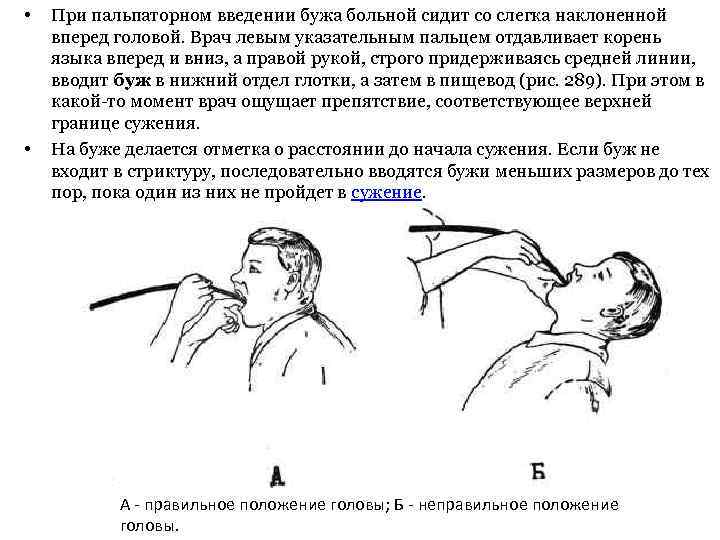

• • При пальпаторном введении бужа больной сидит со слегка наклоненной вперед головой. Врач левым указательным пальцем отдавливает корень языка вперед и вниз, а правой рукой, строго придерживаясь средней линии, вводит буж в нижний отдел глотки, а затем в пищевод (рис. 289). При этом в какой-то момент врач ощущает препятствие, соответствующее верхней границе сужения. На буже делается отметка о расстоянии до начала сужения. Если буж не входит в стриктуру, последовательно вводятся бужи меньших размеров до тех пор, пока один из них не пройдет в сужение. А - правильное положение головы; Б - неправильное положение головы.

• • При пальпаторном введении бужа больной сидит со слегка наклоненной вперед головой. Врач левым указательным пальцем отдавливает корень языка вперед и вниз, а правой рукой, строго придерживаясь средней линии, вводит буж в нижний отдел глотки, а затем в пищевод (рис. 289). При этом в какой-то момент врач ощущает препятствие, соответствующее верхней границе сужения. На буже делается отметка о расстоянии до начала сужения. Если буж не входит в стриктуру, последовательно вводятся бужи меньших размеров до тех пор, пока один из них не пройдет в сужение. А - правильное положение головы; Б - неправильное положение головы.